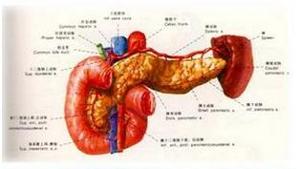

胰腺肉瘤指来源于胰腺间叶组织的恶性肿瘤国内外文献报道的原发性胰腺肉瘤有平滑肌肉瘤、软骨肉瘤、恶性纤维组织细胞瘤、纤维肉瘤、横纹肌肉瘤、恶性神经鞘瘤、血管肉瘤、恶性血管外皮瘤等,均为个案报道。文献报道的胰腺肉瘤以平滑肌肉瘤最多见。检索国内文献CBM1994~2000年共13篇文献,其中原发性胰腺肉瘤个案报道8篇均为平滑肌肉瘤(共6例)胰腺转移性肉瘤5篇,系胃平滑肌肉瘤胰腺转移、成骨肉瘤胰腺转移。

胰腺肉瘤主要的构成成分多起源于胰腺结缔组织血管神经组织。淋巴肉瘤是否来源于胰腺,是否真属于胰腺肉瘤,各家意见不一致。按一般病理分类有纤维肉瘤、平滑肌肉瘤、神经纤维肉瘤、淋巴肉瘤、脂肪肉瘤、恶性神经鞘瘤、网状肉瘤、血管肉瘤、骨髓外浆细胞瘤和横纹肌肉瘤其中以纤维肉瘤最多见。肉瘤可发生于胰腺的任何部位,其恶性程度较胰腺癌低。 ;